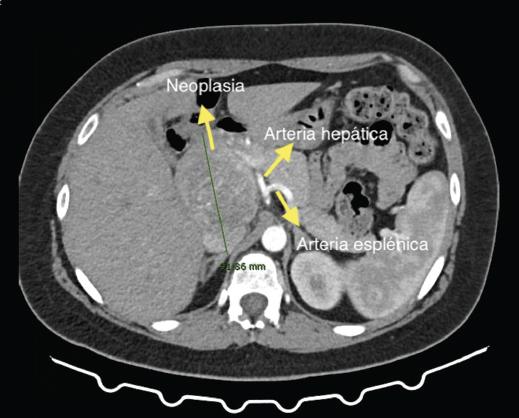

Mujer de 33 años sin antecedentes, estudiada por epigastralgia, diarreas, saciedad precoz y distensión abdominal. Se realiza una analítica que reporta marcadores tumores normales. La tomografía computarizada (TC) (Fig. 1) multifásica con contraste y la resonancia magnética (RM) (Fig. 2) evidencian una lesión a nivel de la cabeza-proceso uncinado del páncreas, hipointensa en T1 e hipertensa en T2, de diámetro mayor de 92 mm, sin asociar dilatación de la vía biliar, atrofia distal glandular ni lesiones a distancia. Se sospecha una neoplasia pseudopapilar sólida del páncreas. Es intervenida quirúrgicamente y se evidencia una gran tumoración, cuya enucleación se desestimó por afectación de la papila duodenal, llevándose a cabo una duodenopancreatectomía cefálica de Whipple (Fig. 3). El estudio anatomopatológico confirmó la resección con márgenes sin invasión ganglionar, vascular ni perineural. La paciente completó el posoperatorio sin incidencias y fue dada de alta al noveno día. Tras 18 meses de seguimiento, persiste libre de enfermedad.

Figura 1 Se aprecia una masa de 92 mm de diámetro anteroposterior, dependiente de la cabeza pancreática, adyacente al tronco celíaco y la arteria hepática, que rodea sin infiltrar.